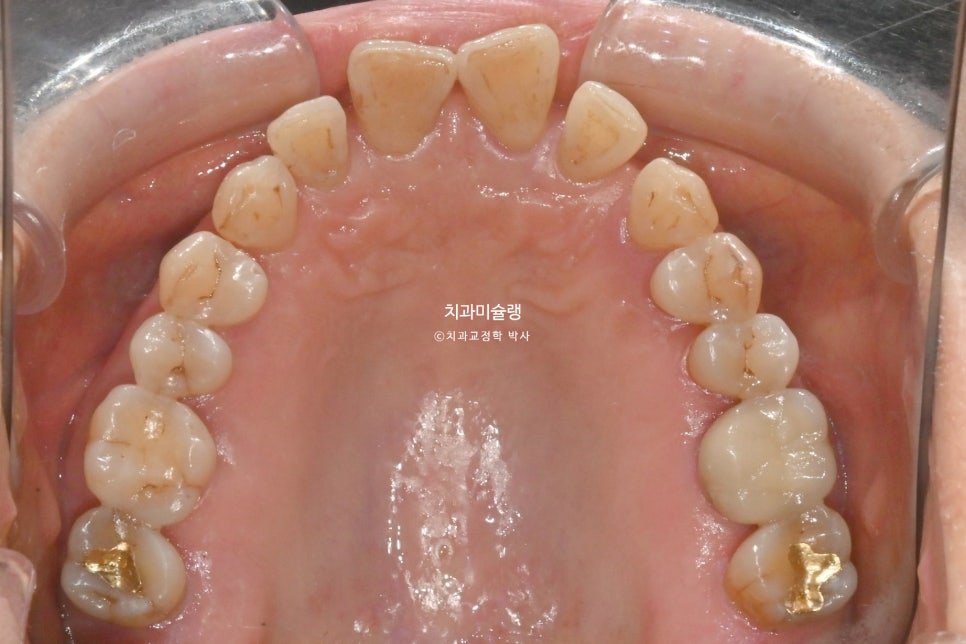

앞니 사이 블랙트라이앵글이 여기저기 보입니다.

앞니들이 벌어진것 뿐만 아니라 회전된, 소위 “나비치아”입니다.

어금니는 배열이나 교합상 문제가 없습니다.

노년교정에서의 중요한 고려사항은 무엇보다 잇몸건강 이죠. 엑스레이상 잇몸이 내려앉은 부분이 여기저기 보이고 뿌리끝 염증이 있는 어금니도 보입니다.